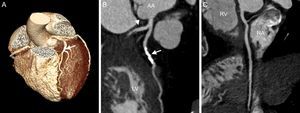

Noncontrast coronary artery CT, such as coronary artery calcium scan, can be performed rapidly (3-5 s breath hold) with a radiation exposure of up to 0.37 mSv, when newer protocols, such as high-pitch scanning and IR, are used.28,29 The advantage of coronary artery calcium scan consists in its highly standardized interpretation (Agatson score determined by the sum of the weighted scores for all coronary arteries multiplied by the maximal lesion density).30 The patient's score is then compared with similar results obtained in asymptomatic persons of the same sex, age, and ethnicity.31 A score above the 75th percentile is considered “high-risk”.32 In symptomatic patients, a negative calcium score is often unreliable in excluding significant CAD, since the coronary artery calcium scan is unable to visualize noncalcified plaques, which may attain marked obstructive severity in 1% to 3% of patients.33,34 Therefore, for most practitioners, CCTA remains the diagnostic modality of choice in evaluating ACS (Figure 2).

Cardiac computed tomography of a 72-year-old female patient presenting with acute chest pain to the emergency department. A: Prospective, elecrocardiogram-triggered computed tomography angiography (100kV, 1.8 mSv). B: Curved multiplanar reconstruction shows a significant luminal narrowing due to a calcified plaque in the left anterior descending artery. C: No coronary plaque or stenosis in the proximal circumflex (arrowhead). No coronary plaque or stenosis is detected in the right coronary artery. AA, ascending aorta; LV, left ventricle; RA, right atrium; RV, right ventricle.